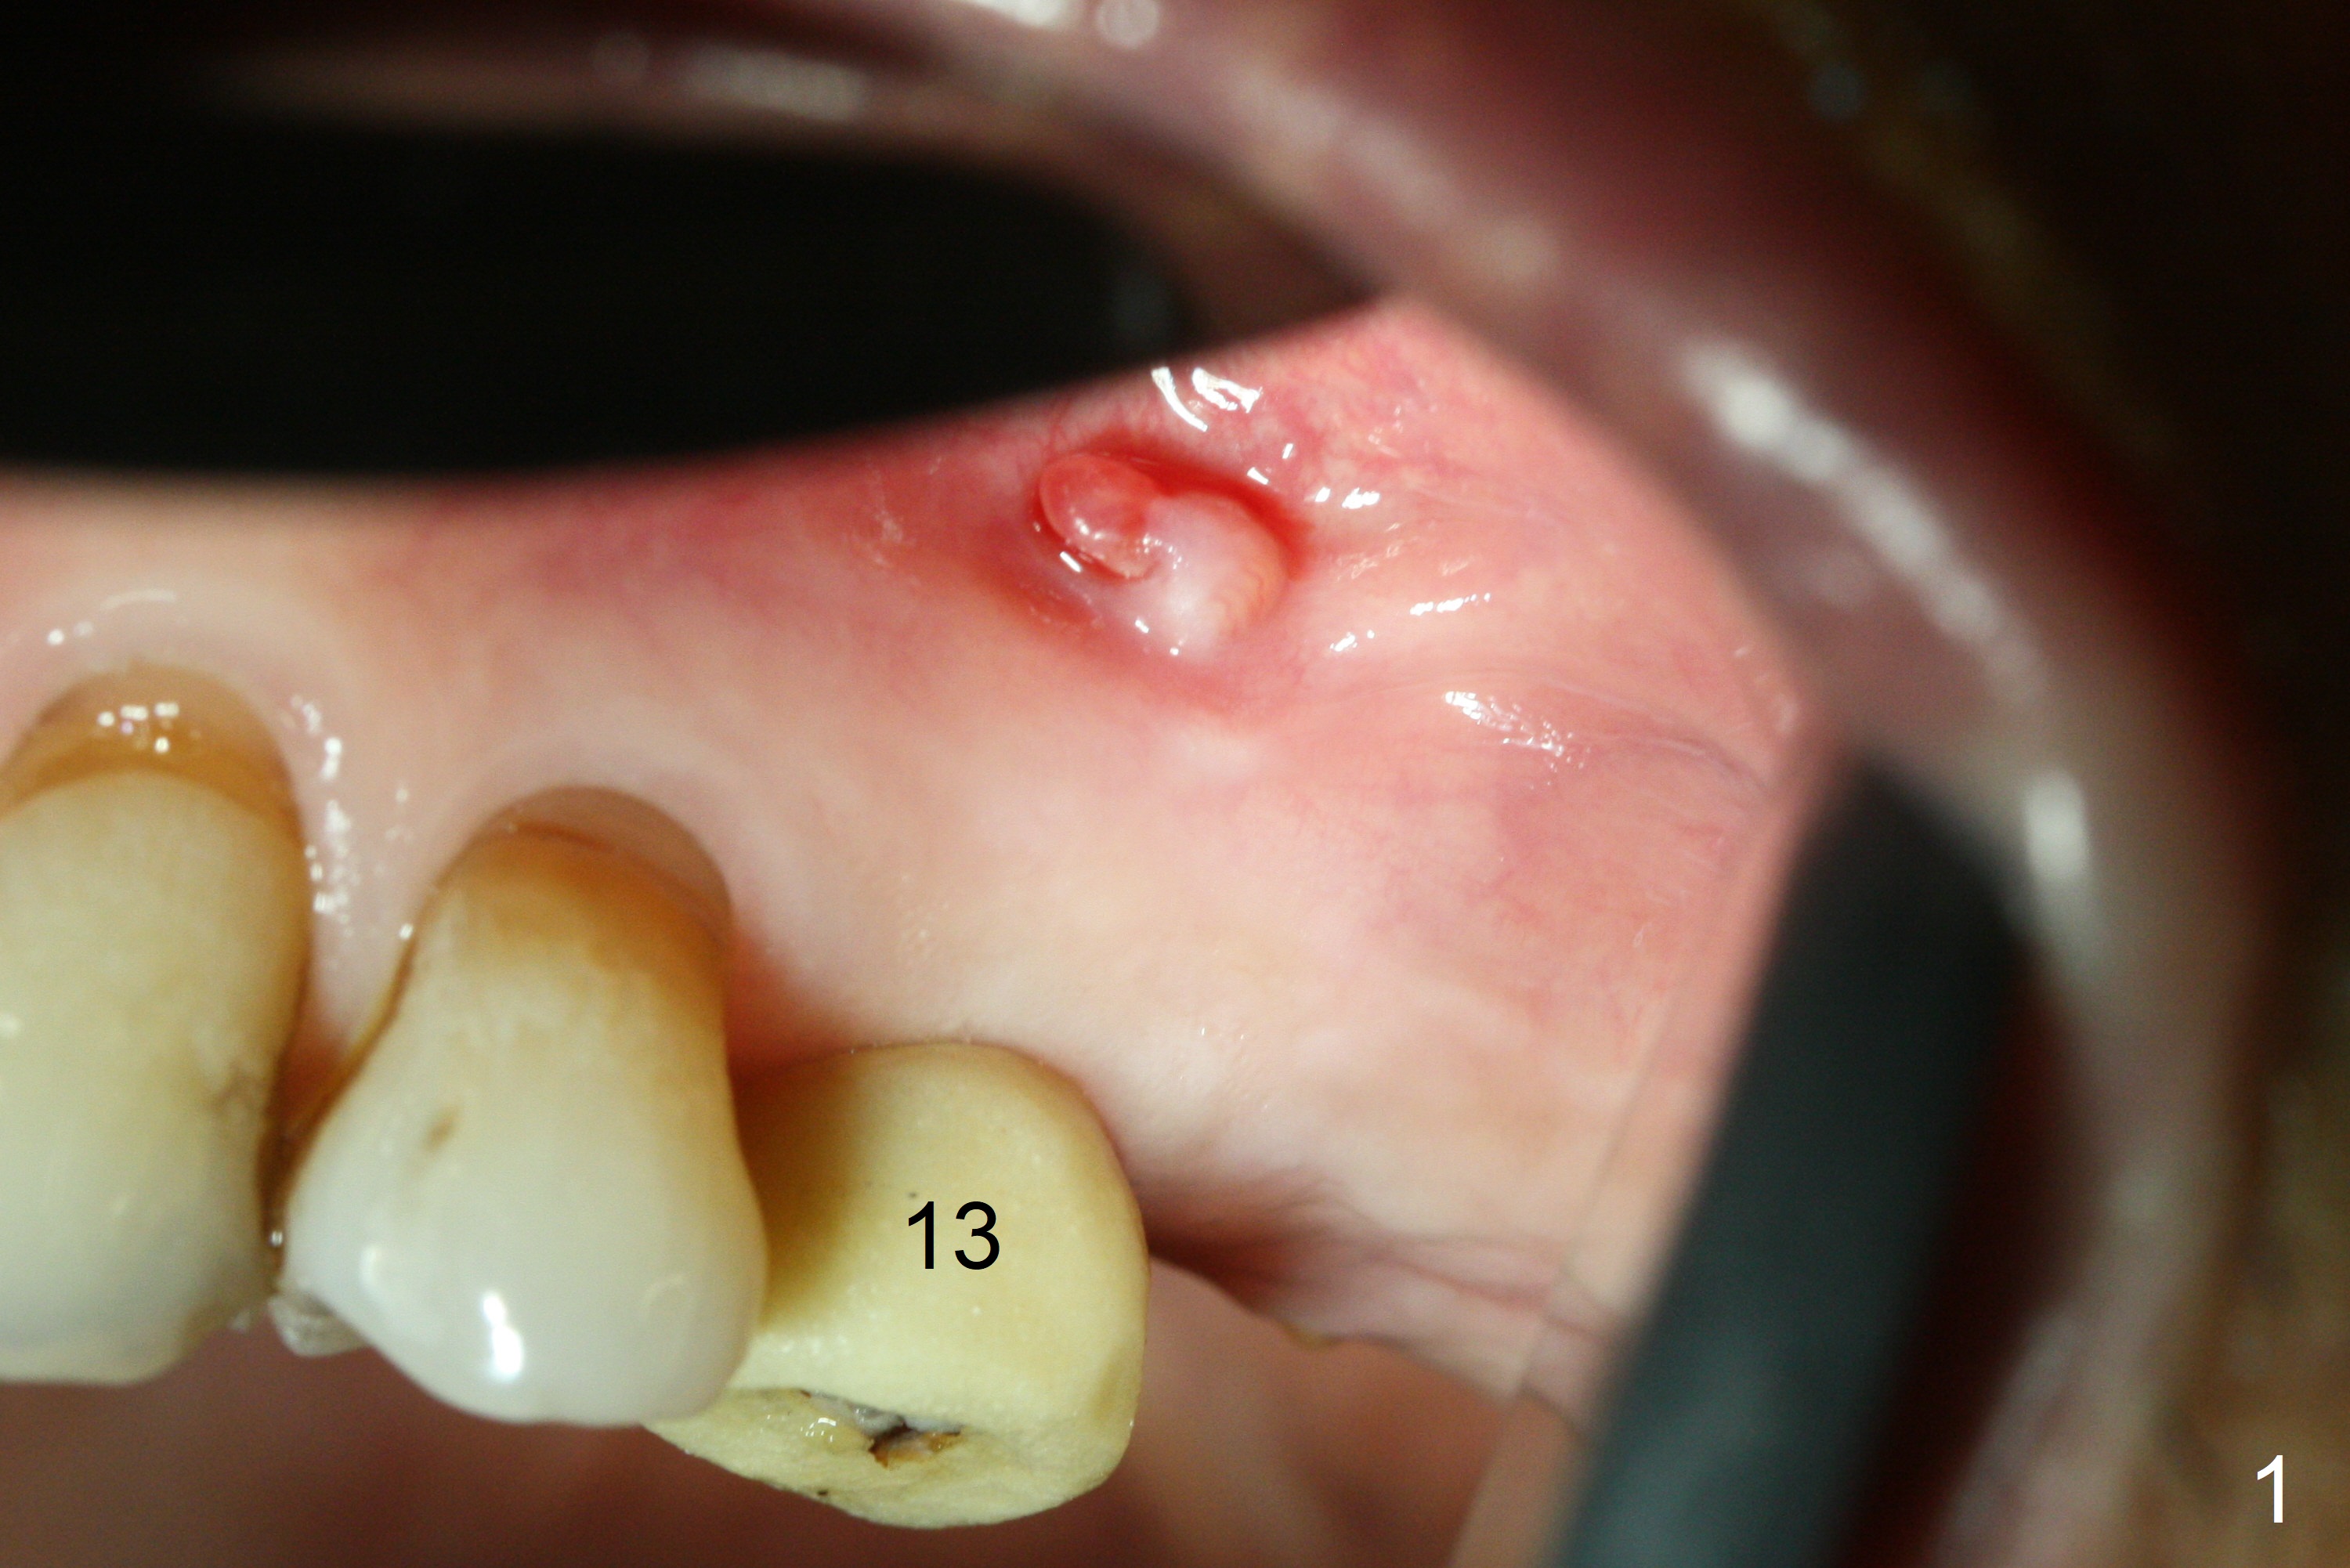

A fistula is found apical to #13 immediate implant 9 months postop (Fig.1).  It is curetted without bony defect.  Osteotomy at #15 is accomplished with traditional tapered osteotomes from 2 to 5 mm for 11 mm deep.  Although the patient is a little uncomfortable with tapping (as compared to Magic Expanders), a 4.5x11 mm dummy implant is placed 2 mm subgingival with primary stability (Fig.2).  Finally a 5x11 mm IBS implant (2 mm longer than the previous one) is placed with insertion torque > 50 Ncm; a 6x2 mm healing abutment is placed (Fig.3,4).  The advantages of the flapless surgery (because of the wide ridge) include no allograft or suture.  The fistula apical to #13 implant disappears 3 days postop (Fig.5), while the gingiva attaches to the healing abutment at #15 (Fig.6).